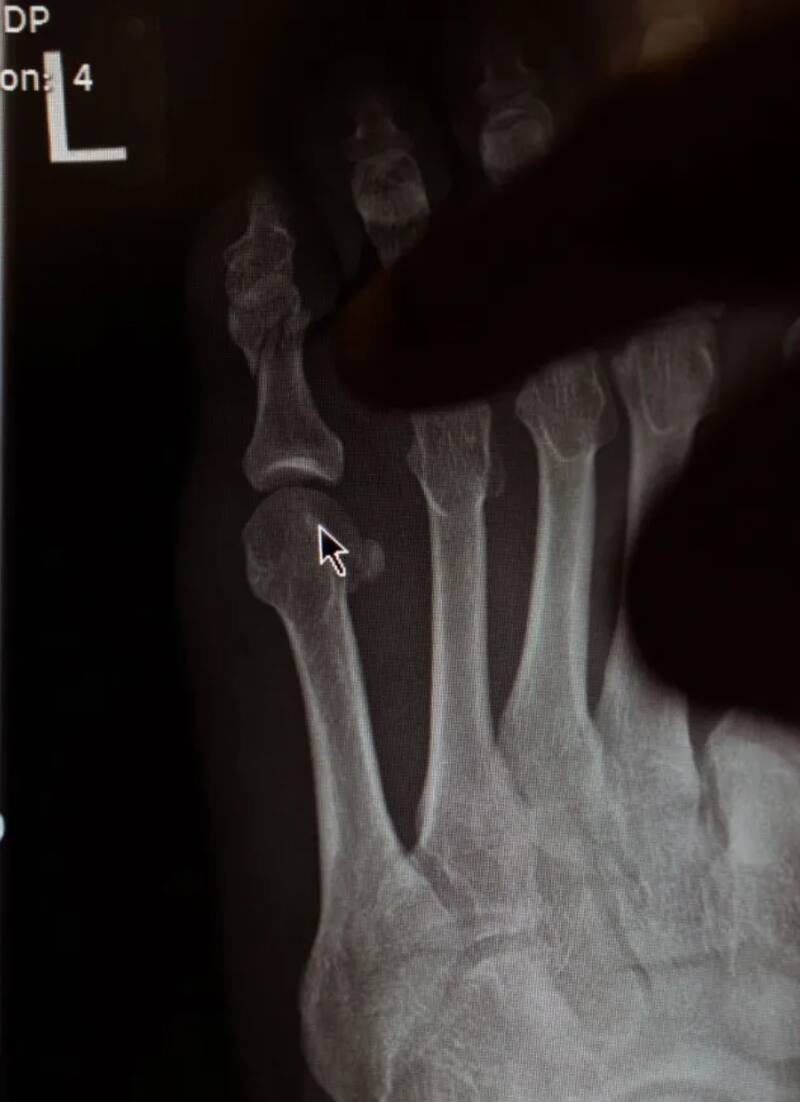

A través de su cuenta oficial de X, el irlandés subió una captura en la que reveló una pequeña fractura en el dedo meñique del pie. La insólita lesión dejó acomplejado al luchador, quien comentó que se debió por haber entrenado sin protección en sus pies. “Estaba muy preparado para esta pelea, esto es muy doloroso de asumir. Estaba entrenando sin la protección necesaria y al dar una patada me rompí el dedo. Necesito unas semanas y estaré de vuelta”, indicó.